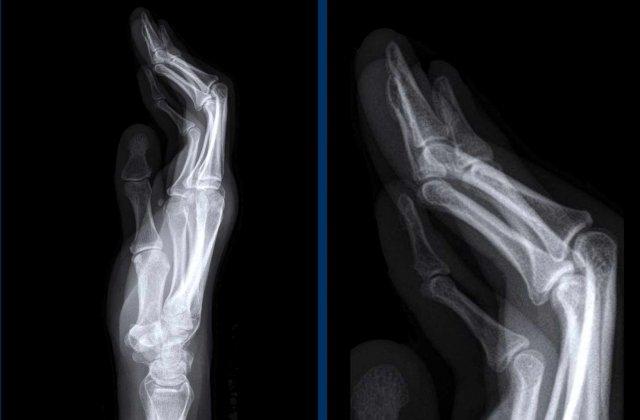

Biến dạng bút chì trong cốc

Trong viêm khớp vảy nến, sự kết hợp giữa bào mòn bờ khớp và tăng sinh xương có thể tạo ra biến dạng bút chì trong cốc.

Ngón xúc xích

Hình ảnh điển hình của viêm ngón tay (dactylitis) “ngón xúc xích” với phù nề mô mềm và biến dạng bút chì trong cốc tại khớp liên đốt xa (DIP) 1-2 và 5 của bàn tay trái ở bệnh nhân viêm khớp vảy nến.

Lưu ý rằng các khớp bàn ngón tay (MCP) không bị tổn thương (khác với viêm khớp dạng thấp).

Viêm khớp vảy nến tiến triển

- Hình bên trái cho thấy bào mòn xương ở rìa khớp (mũi tên đen) và hình thành xương mờ nhạt (mũi tên xanh) tại khớp liên đốt ngón (IP).

- Về sau, bệnh tiến triển thành biến dạng bút chì trong cốc điển hình.

Phân bố tổn thương và sự hình thành xương khiến chẩn đoán viêm khớp dạng thấp ít có khả năng.

Các bào mòn xương ở rìa khớp và sự vắng mặt của tổn thương khớp liên đốt xa (DIP) ở các khớp khác khiến chẩn đoán viêm xương khớp bào mòn ít có khả năng, mặc dù biến dạng bút chì trong cốc có thể trông giống biến dạng cánh hải âu trong viêm xương khớp bào mòn.

A. Biến dạng bút chì trong cốc tại ngón chân thứ 1 và thứ 5.